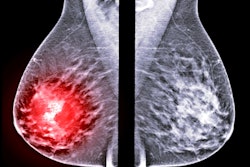

Contrast-enhanced digital mammography (CEDM) may be an excellent choice for staging breast cancer before surgery. The imaging modality had high sensitivity and specificity in a large-scale study published on 30 January in the Breast Journal.

The study included 326 women with breast cancer who had presurgical contrast mammography instead of MRI or another imaging modality. The use of CEDM changed the initial surgical plan in almost one-fifth of patient cases.

CEDM detected all but four lesions for an overall sensitivity of 98.8%. Findings from CEDM imaging resulted in 23.6% of patients getting a second ultrasound scan and 17.5% undergoing an additional biopsy.

The imaging method changed the initial surgical plan for 18% of patient cases. Patients with a changed plan often received a more extensive breast-conserving surgery or converted from breast-conserving surgery to a mastectomy.

However, CEDM also led to four false-negative diagnoses and three false-positive diagnoses, although the authors noted the false negatives were not missed by CEDM but were cases with positive margins on the surgical specimens. CEDM also performed significantly better for palpable lesions than nonpalpable ones.